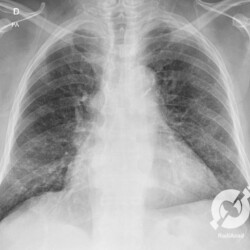

Aumento do volume cardíaco, lesões intersticiais reticulares e consolidações alveolares nos lobos inferiores, com obliteração do seio costofrênico direito.